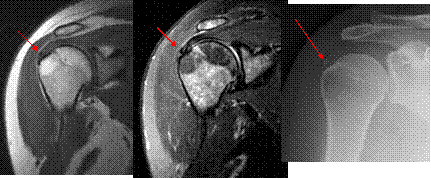

Calcific tendinopathy

Don’t forget to look at the x-rays!